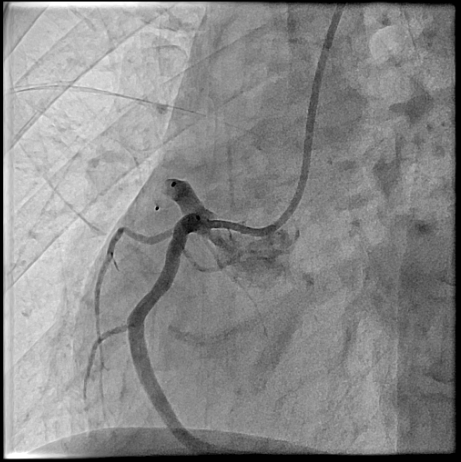

The procedure was performed via left radial artery access. The right coronary fistula was engaged with a 6F AL1 guide catheter. A 5F microcatheter advanced an ASAHI Sion Black wire into the fistula tract. Given the fistula¡¯s large size and high flow, a two-device closure strategy was employed. A 7-mm AMPLATZER Vascular Plug 4 was initially deployed proximally, achieving partial flow reduction. To ensure complete occlusion, an 8-mm AMPLATZER Vascular Plug was subsequently positioned at the ostium. Final angiography confirmed marked flow reduction in the fistula while preserving native RCA flow. The small LAD fistula was left untreated due to minimal shunting. The procedure was completed without complications, and radial hemostasis was achieved.

Large coronary arteriovenous fistula cause heart failure by chronic volume overload from left-to-right shunting. Transcatheter closure offers definitive treatment while avoiding surgical risks. In this case, a dual-plug technique achieved complete occlusion of a high-flow fistula without compromising coronary perfusion. Symptom resolution after the procedure, combined with guideline-directed medical therapy, underscores the importance of eliminating hemodynamic burden in fistula-related heart failure with reduced ejection fraction. This case supports percutaneous closure as a safe, effective strategy in selected patients.